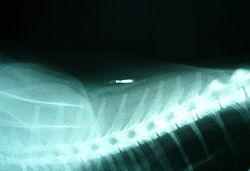

زرع رقاقة فى جسم حيوان

رقاقة مزروعة في قطة.

إن زرع رقاقة هو التعرف على الدوائر المتكاملة التى توضع تحت الجلد لكلب ، أو قط ، أو حصان ، أو الحيوانات الأخرى. والرقائق حوالى حجم حبة كبيرة من الأرز ، وتستند إلى إيجابيات RFID (التكنولوجيالتحديد الهوية بترددات الراديو) .